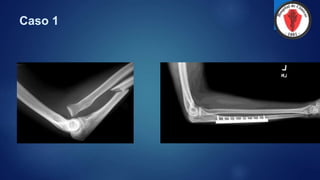

Caso 1

 Paciente femenina de 78 años la cual mientras deambula sufre caída que le produce trauma

indirecto del codo derecho que se acompaña de dolor, aumento de volumen e incapacidad

funcional, responda:

 Clasificación de la fractura

 Evaluación clínica:

 Evaluación radiográfica